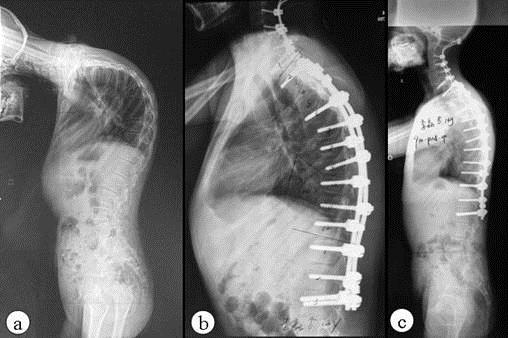

AS ①晚期 ②重度 病史:5年+

治疗后骶髂关节疼痛消失,腰椎前屈、背伸侧弯活动自如,膝关节无压痛感,复查血沉、C反应蛋白、等各项检查均已达到临床康复的标准。